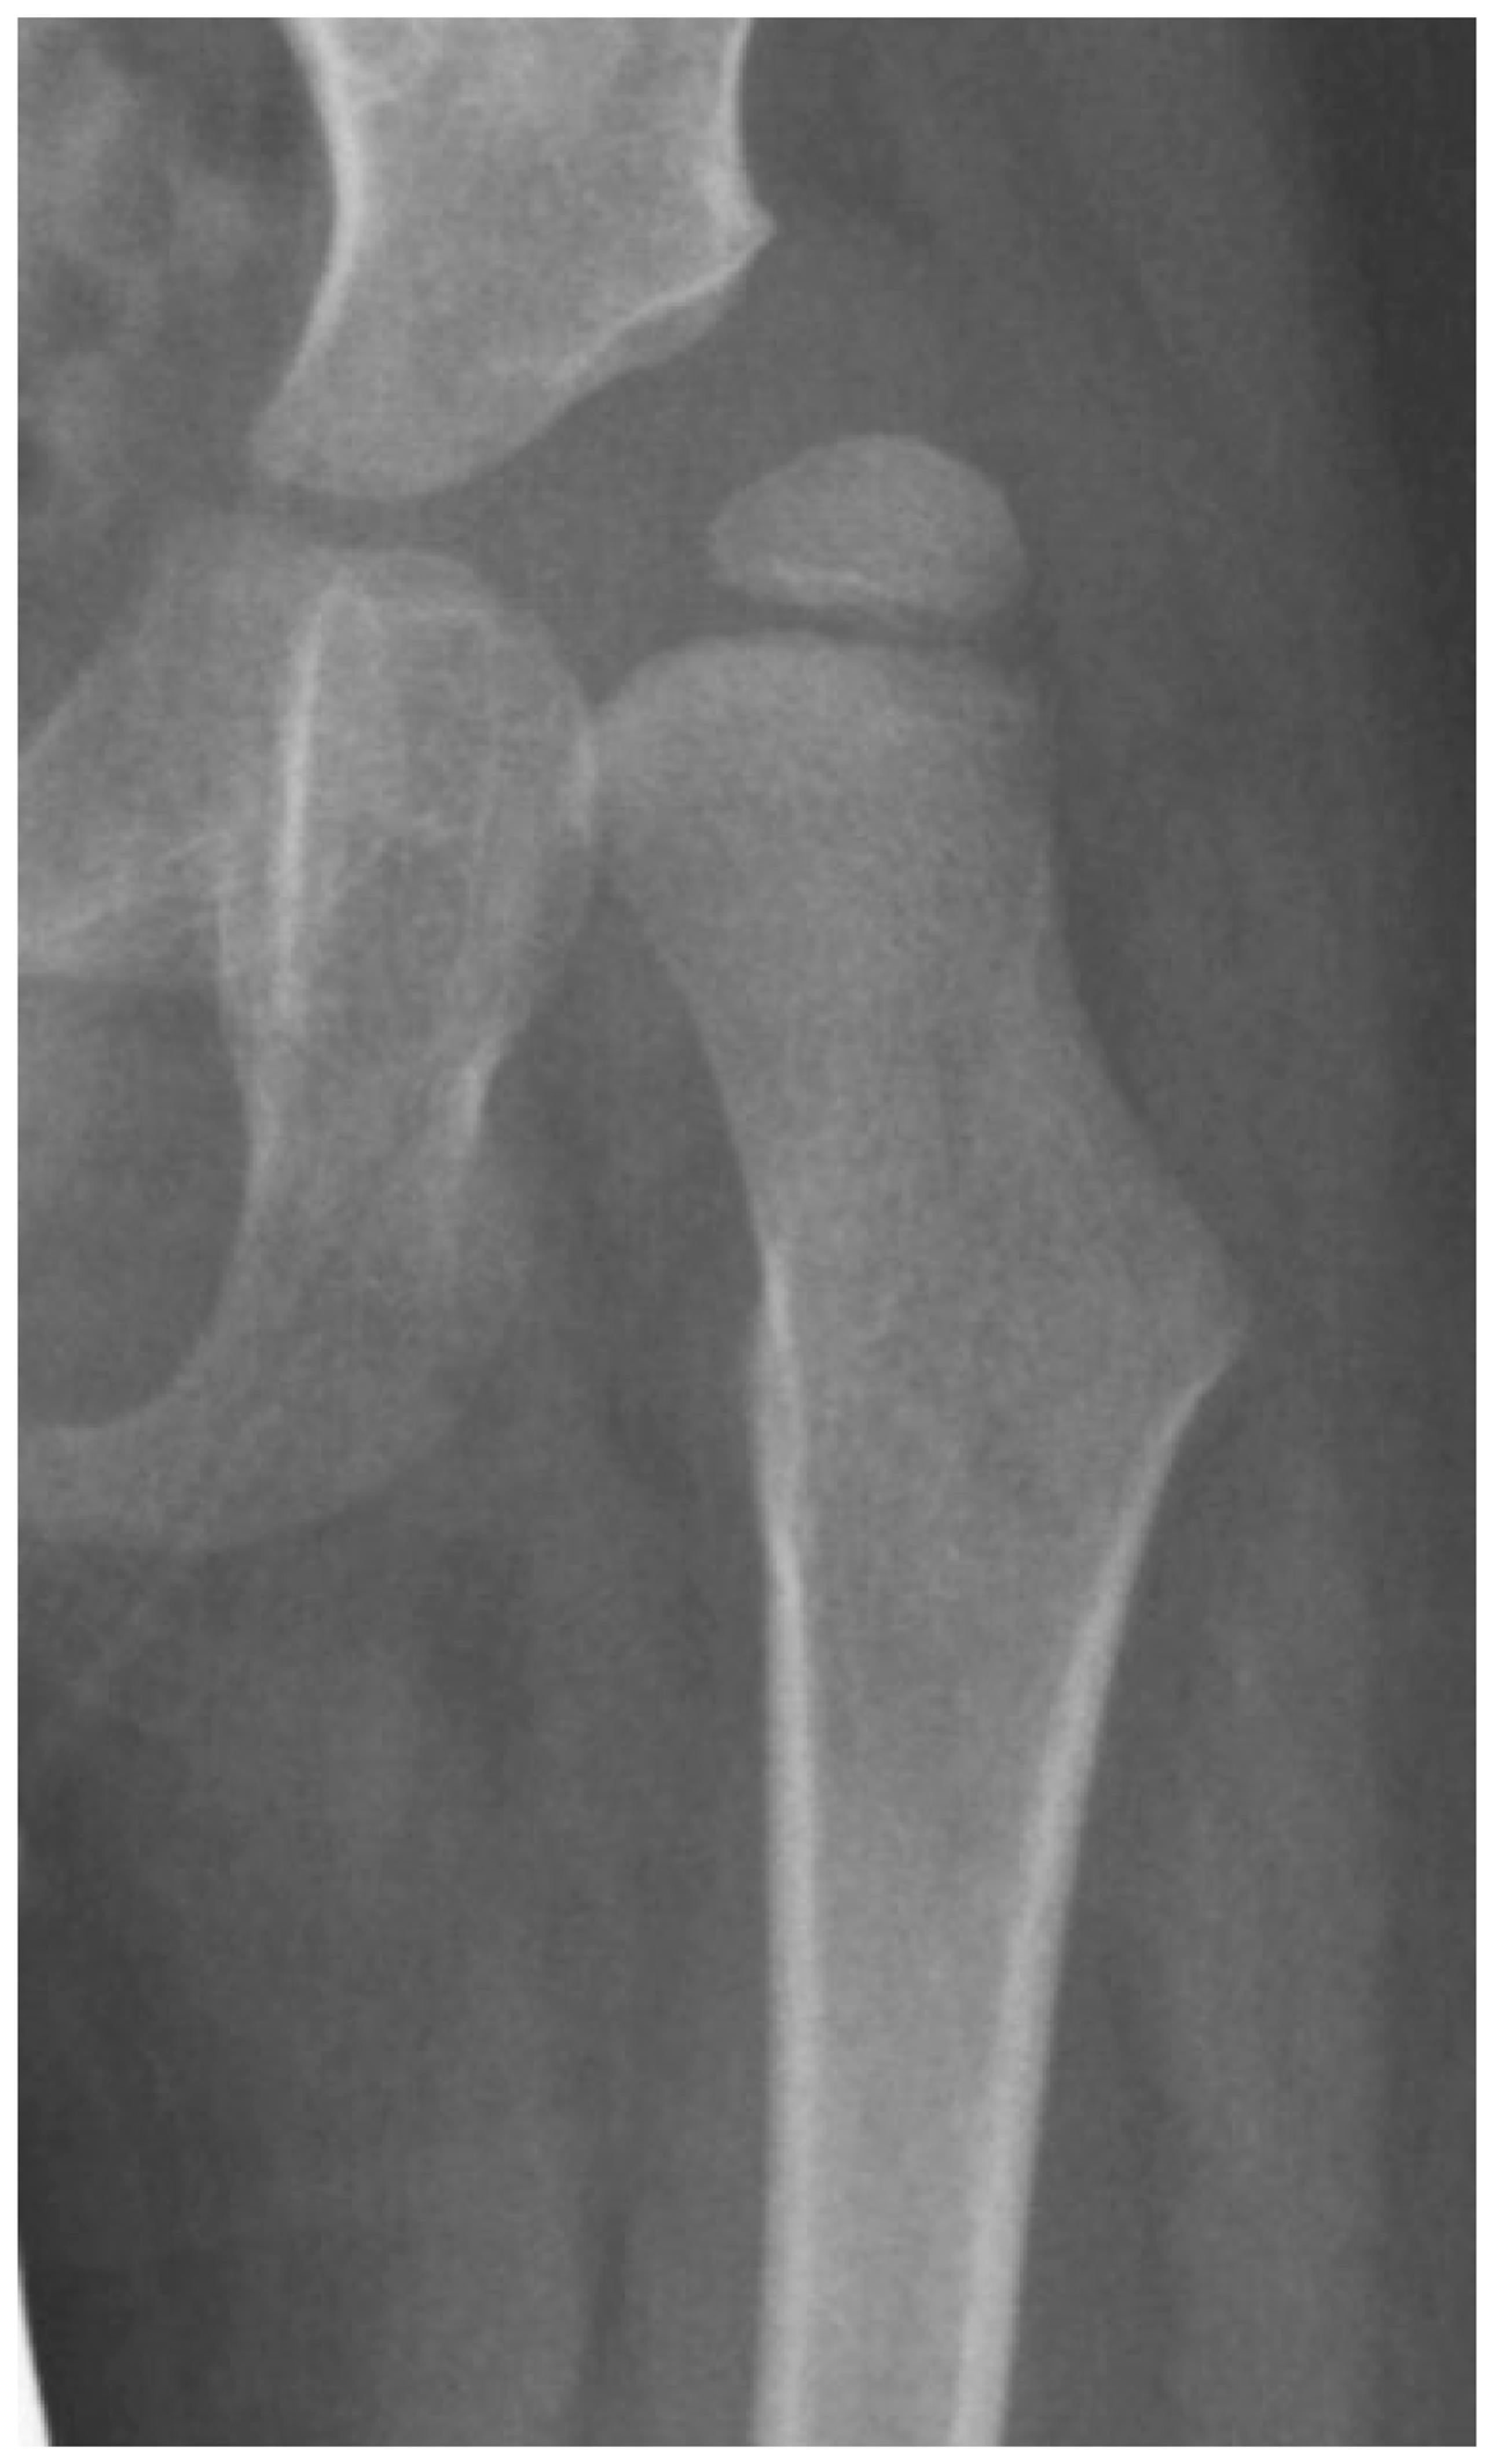

3.4. Femoral Factors Influencing Hip Pathology

3.4.1. Pathologic Role of Femoral Anteversion

3.4.2. Pathologic Role of Coxa Valga and the Impact of its Correction on Spastic Hips